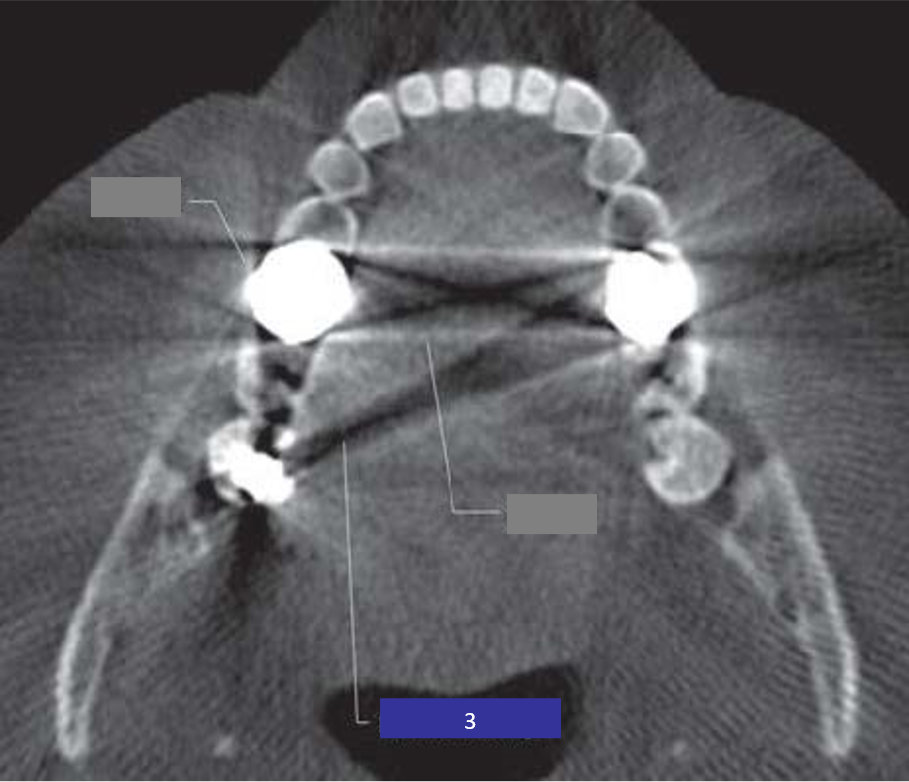

35) Identify the cone beam artifact indicated by 1 in this image? (1 mark)

36 / 46

36) Identify the cone beam artifact indicated by 2 in this image? (1 mark)

37 / 46

37) Identify the cone beam artifact indicated by 3 in this image? (1 mark)